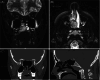

Giant Cell Tumor of the Inferior Turbinate in a 12-Year-Old Child: First Case Report

Figures